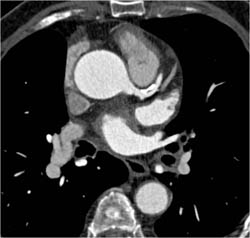

Diagnosis

Diseased LAD